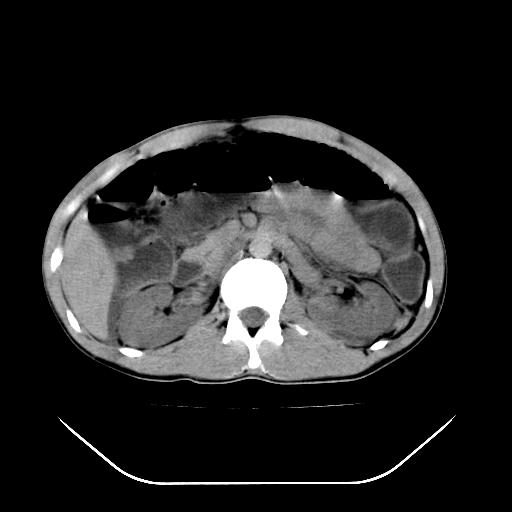

m-25y 高空堕落 12 月5号

12月7号病人尿量200ml/24h 急查双肾ct

左肾挫裂伤并肾周血肿;

肝肾间隙可见液区,建议手术探查;

左肾挫裂伤并肾周血肿

支持 : 左肾挫裂伤并肾周血肿

支持:1、左肾挫裂伤并肾周血肿;

2、少量腹水;

3、左肾旋转不良;

4、反射性肠淤张。